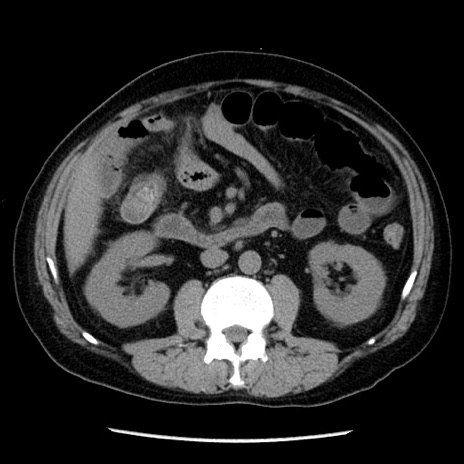

症例29(横断像)

【症例】40歳代男性

【現病歴】2日前から胃痛あり。徐々に周期的な激痛に変化した。本日になっても激痛があるため受診。

【身体所見】意識清明、BT 38-39℃台あり、腹部:膨満、やや硬、右下腹部に圧痛あり。

【データ】WBC 8500、CRP 23.26